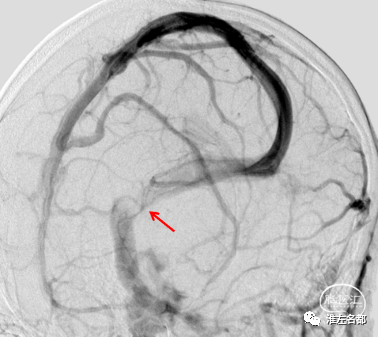

经右侧颈动脉造影(正位):

右侧横窦远端、乙状窦和右侧颈内静脉远段显影不清,提示血栓闭塞。